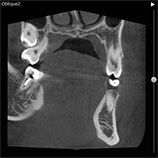

当クリニックでは歯科用CT装置を導入しています。

歯科用の3次元CTにより、いままで以上に詳細な診断ができるようになりました。

インプラント、歯周病、根管治療(歯の根の治療)、顎関節症などの治療時に有効です。

※CT画像一例